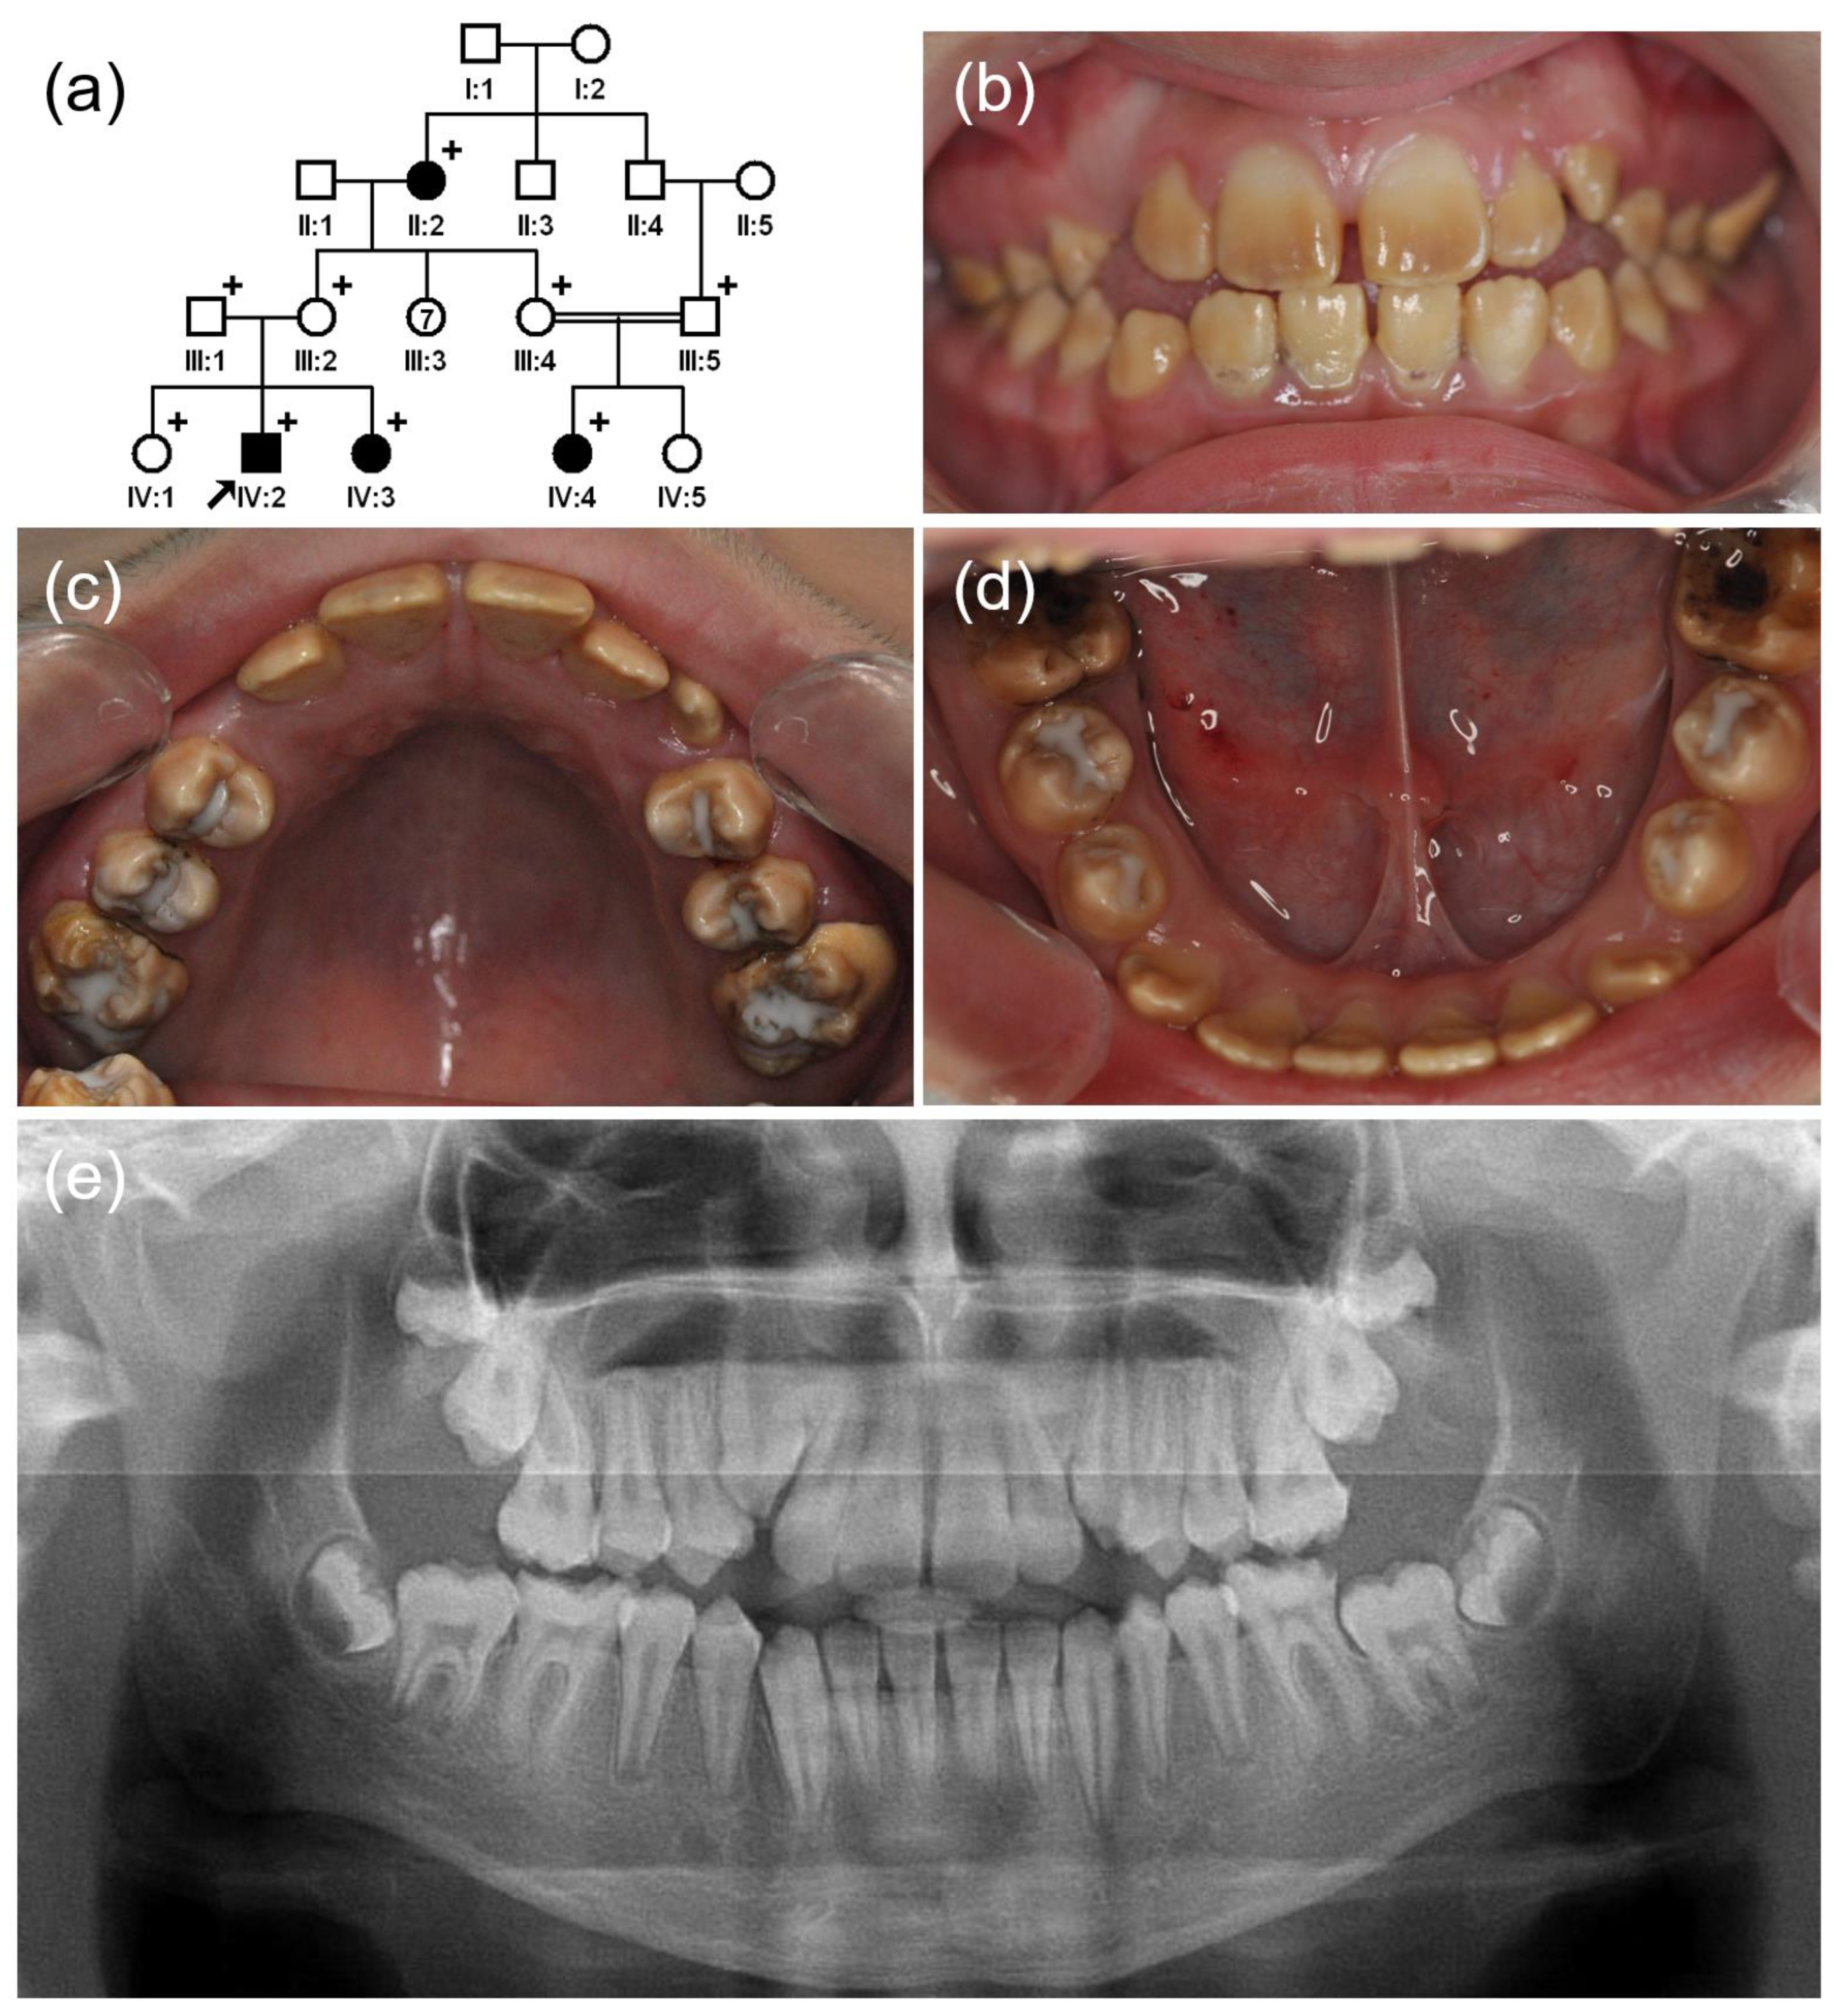

3.1. Family 1